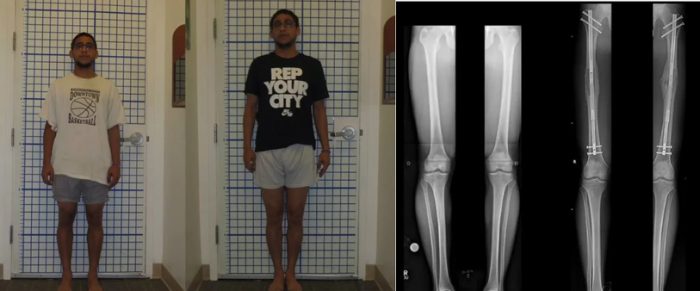

ଭୁବନେଶ୍ୱର: ସମୟ ଅନୁସାରେ ମନୁଷ୍ୟ ପରିବର୍ତନଶୀଳ ହୋଇଥାଏ । ଏବେ ଅନ୍ୟଠାରୁ ସବୁ ଦୃଷ୍ଟିକୋଣରେ ଉନ୍ନତ ହେବା ପାଇଁ ଯୁବପିଢ଼ୀଙ୍କ ନିକଟରେ ଏକ ପ୍ରକାର ପ୍ରତିଦ୍ୱନ୍ଦ୍ୱିତା ଲାଗି ରହିଛି । ଏବେ ୟୁରୋପୀୟ ଦେଶଗୁଡିକରେ ଏକ ଅଜବ ଝୁଙ୍କ ଟେକ କମ୍ପାନୀର ସଫ୍ଟୱେୟାର ଇଞ୍ଜିନିୟରଙ୍କ ନିକଟରେ ଦେଖିବାକୁ ମିଳିଛି । ରିପୋର୍ଟ ମୁତାବକ ଡେଙ୍ଗା ହେବା ପାଇଁ ଏମାନେ ଲକ୍ଷ ଲକ୍ଷ ଟଙ୍କା ଖର୍ଚ୍ଚ କରିବା ସହ ଗୋଡରେ ଅପରେଶନ କରାଇବାକୁ ପଛାଉ ନାହାନ୍ତି । ଲିମ୍ବପ୍ଲାଷ୍ଟ ନାମକ ଏକ ସଂସ୍ଥା ଏହି ଅପରେଶନ କରୁଛି । ଏହାର ଡାକ୍ତରଙ୍କ ମତରେ ପ୍ରତ୍ୟେକ ଦିନ ରୋଗୀଙ୍କ ସଂଖ୍ୟା ବଢ଼ିବାରେ ଲାଗିଛି । କରୋନା ମହାମାରୀ ପରେ ଏହି ଟ୍ରେଂଣ୍ଡ ଜୋର ଧରିଛି । ପାଖାପାଖି ୬୦ ଲକ୍ଷ ଖର୍ଚ୍ଚରେ ଜଣେଙ୍କ ଶରୀର ୩ରୁ ୬ଇଂଚ ପର୍ଯ୍ୟନ୍ତ ବଢ଼ିପାରିବ ।

ଏଥିପାଇଁ ରୋଗୀର ଜଙ୍ଘ ହାଡକୁ ପ୍ରଥମେ ଭଙ୍ଗା ଯିବା ପରେ ଏହାକୁ ମେଟାଲ ନେଲ ଦେଇ ଯୋଡା ଯାଇଥାଏ । ୩ ମାସ ଅପରେଶନ କାଳ ମଧ୍ୟରେ ମେଟାଲ ନେଲ ମ୍ୟାଗ୍ନେଟିକ ରିମୋଟ କଂଟ୍ରୋଲ ଦ୍ୱାରା ଧିରେ ଧିରେ ବୃଦ୍ଧି କରାଯାଇଥାଏ । ଏହା ପରେ ହାଡଗୁଡିକୁ ମଜଭୁତ କରିବା ପାଇଁ ରୋଗୀଙ୍କ ନିର୍ଦ୍ଦିଷ୍ଟ ସମୟ ପର୍ଯ୍ୟନ୍ତ ବିଶ୍ରାମ ଏବଂ ଔଷଧ ଖାଇବାକୁ କୁହା ଯାଇଥାଏ । ବିଶେଷଜ୍ଞଙ୍କ ମତରେ ଏଥିରେ ଗୋଡର ଲମ୍ବା ବଢ଼ିବା ସତ, କିନ୍ତୁ ଏହାର ହାଡ ଦୁର୍ବଳ ହୋଇ ପଡିବ । ଯାହାକି ପରିଣତ ବୟସରେ ଅସୁବିଧା ସୃଷ୍ଟି କରିପାରେ । ମହିଳାଙ୍କ ଅପେକ୍ଷା ପୁରୁଷମାନେ ଏହି ଅପରେଶନ ପ୍ରତି ବିଶେଷ ଆଗ୍ରହ ପ୍ରକାଶ କରୁଛନ୍ତି ।